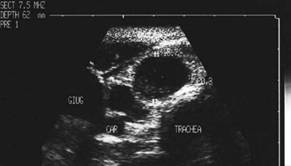

Femeie de 70 ani. Disfonie progresiva prin

paralizie de recurent drept. Nodul voluminos (35 x 25 x 43 mm, 19 cc) care ocupa

aproape complet lobul drept, neomogen, hipoecogen, cu arie anterioara

hipoecogena. Lob stang nevizuzlizat (probabil agenezie). Calcitonina =

820 pg/ml. (v.n. <10pg)

CEA= 638 ng/ml (v.n. <8 ng).

Examen citologic prin citoaspiratie: carcinom midolar cu celule spindle.

CT – aceeasi pacienta – agenezie lob stang